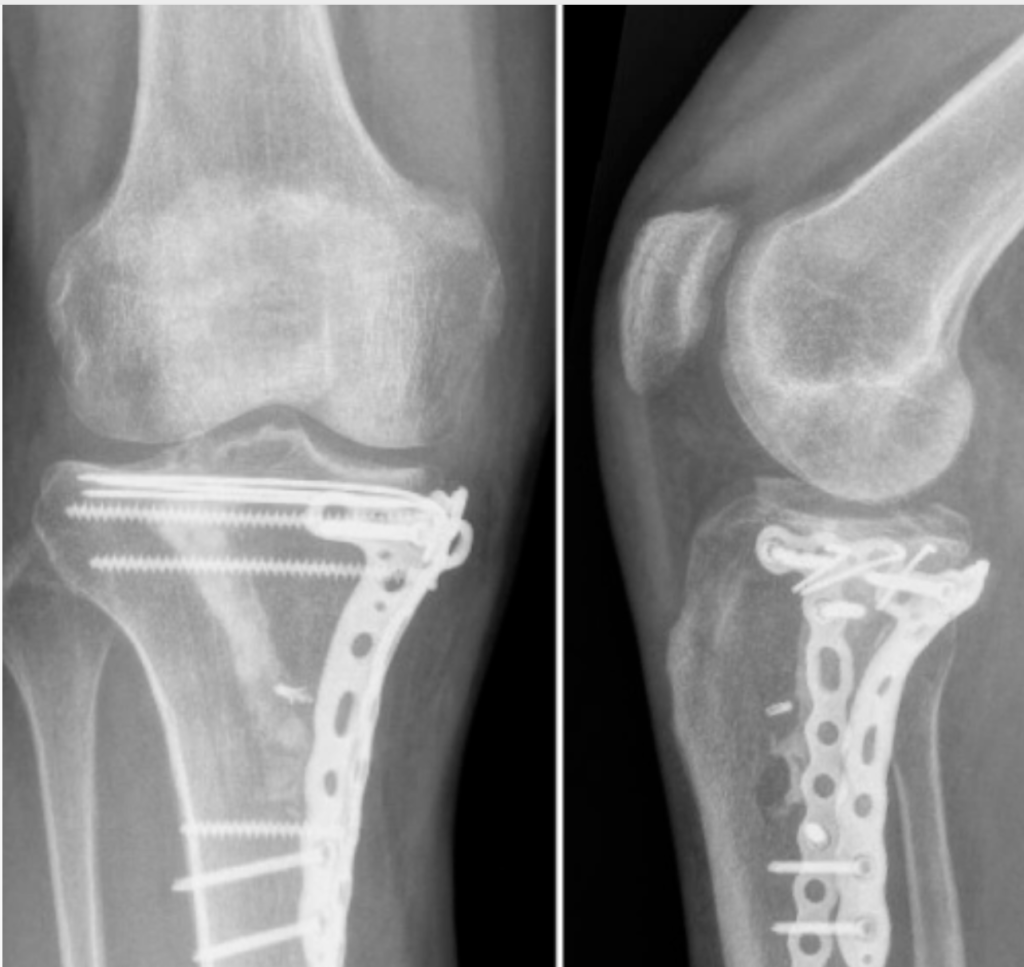

Historically, delayed weight-bearing (10–12 weeks post-op) was standard, primarily to protect weak fixation constructs. But modern innovations — like locking compression plates (LCP) and angle-stable screws — changed the game.

- Confirm by postoperative X-ray or CT:

- <2 mm joint surface collapse

- No hardware loosening or misalignment

- Modern locking plates allow controlled partial loading early (20–30% body weight).